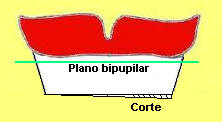

- Verifique en el plano frontal, si el plano de

oclusión es paralelo a la línea que une las pupilas de nuestro

paciente (plano bipupilar)

En color verde línea

bipupilar |